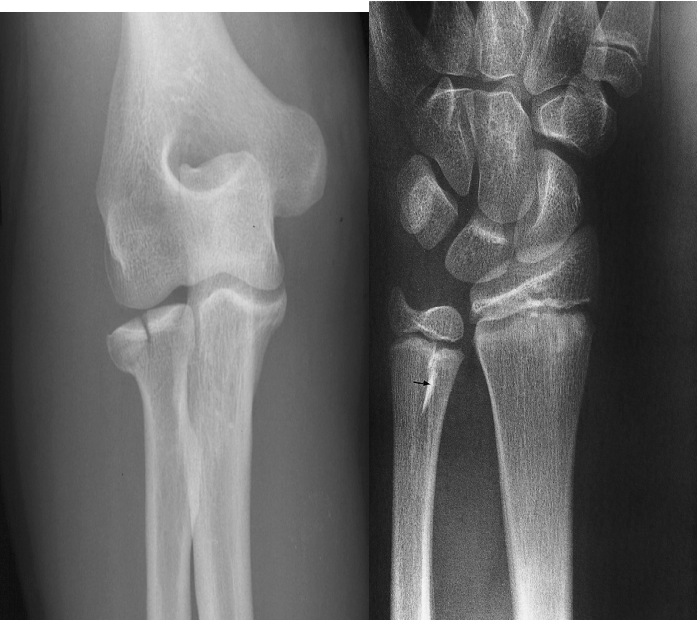

On Plain radiographs fractures may be recognized or suspected by several signs :

A. Fracture of the head of the radius appearing as a lucent line.

B. Fracture of the lower ulnar metaphysis appearing as a sclerotic line (small black arrow).